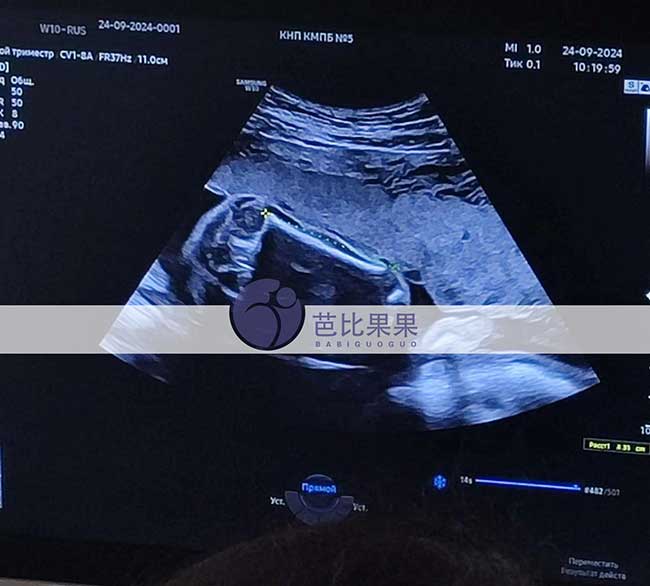

山东X先生出国助孕匹配的乌克兰试管妈妈做孕24周四维彩超

山东X先生出国助孕匹配的乌克兰试管妈妈到医院做孕24周四维彩超,笑容甜美,对自己和宝宝都非常有信心